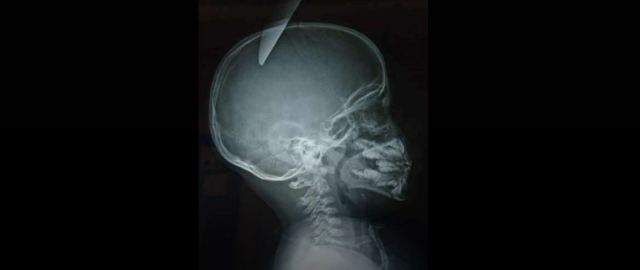

Un menor de cinco años ingresó en el Hospital General de Mexicali, de Baja California, México, después de que un amigo suyo de ocho años le clavara un cuchillo en el cráneo cuando estaban jugando juntos.

Los servicios de emergencia se encontraron al pequeño en estado muy grave y desangrándose, por lo que consideraron trasladarlo de urgencia a un hospital norteamericano. Sin embargo, se desestimó esta posibilidad ya que se consideró que el niño podría no sobrevivir al vuelo. Finalmente fue remitido al citado hospital azteca.

Tras los exámenes médicos, los especialistas determinaron que el niño tenía una herida punzocortante en la región craneal parietal izquierda de 3.80 centímetros de profundidad que ponía su vida en riesgo, tal y como informó el medio local 'Domingo 7'

Tras una intervención los médicos lograron extraerle con éxito el cuchillo y esperan darle de alta en los próximos días.